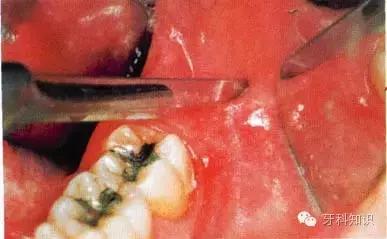

a第Ⅱ类,b分类中位阻生。左下颌第三磨牙阻生,位于黏膜下。磨牙后区切开后,作近中切口,使用12号刀片沿牙龈扇贝状外形切透龈沟至牙槽嵴顶,避免将龈乳头切除。图中近中切口延长至第二前磨牙,便于翻瓣,更好地显露磨牙后区的骨质

b翻瓣后,阻生牙的(牙合)面位于第二磨牙颈部及其牙槽嵴顶均清晰可见。切割牙体前先去除舌侧骨板以保护软组织

c使用纺锤形的车针( Komet - H162A.314),显露其最大周径至釉牙骨质界。车针末端应进入牙槽窝内壁